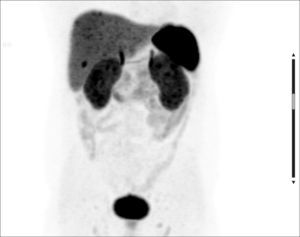

Se presenta un paciente de 73 años operado de cáncer de próstata, actualmente con elevación del antígeno prostático específico (PSA), al que se le realizó una tomografía computada por emisión de positrones (PET/TC) con 18F-colina en el abdomen y pelvis para la reestadificación.

En el plano coronal en proyección de máxima intensidad (MIP) del estudio se puede imaginar la cara de un can raza Border Collie: la captación de ambos riñones semeja las marcas perioculares, mientras que las captaciones del hígado y el bazo parecen las orejas y la acumulación del radiofármaco excretado en la vejiga se asemeja al hocico.